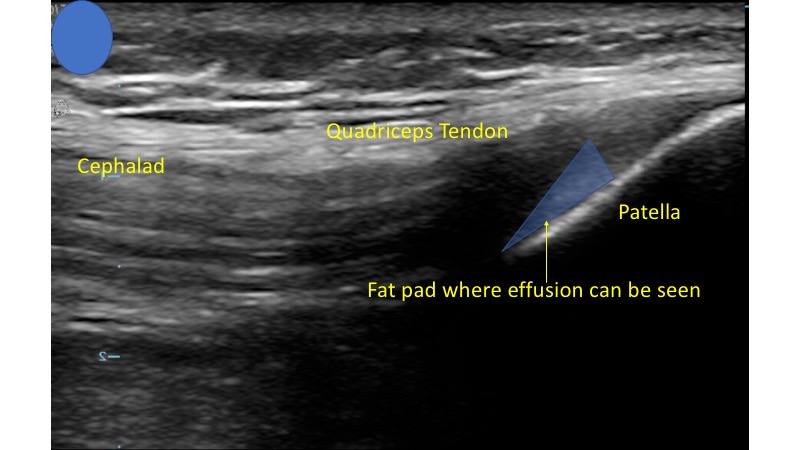

- The anatomy of ultrasound guided knee arthrocentesis involves the quadriceps femoris tendon which will be attached to the patella distally and the quadriceps muscle more proximally.

- You should also be able to identify the femur which will usually lie directly under the quadriceps muscle and the quadriceps tendon.1,4

- In-between the femur and quadriceps femoris tendon is an important fat pad, which is flanked by the patella more distally.

- This area is called the suprapatellar space and will be the location in which you will attempt to aspirate fluid.

- In this view you should be able to identify the quadriceps tendon attached to the patella.

- Deep to the tendon and proximal to the patella you should be able to identify the suprapatellar fat pad superficial to the femur. (Fig. 4)

- Figure 4. Ultrasound demonstrating normal knee

- This will be displaced by joint effusion when a significant amount of fluid exists in this space.4 (Video 1)